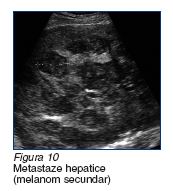

e. melanomul hepatic secundar

este adesea multicentric, cu dimensiuni peste 3 cm. Delimitarea de restul parenchimului este necaracteristica, variabila. Poate avea un caracter

difuz sau circumscris. Structura tumorii, mai frecvent neomogena, cu ecouri de intensitate medie sau joasa.

Atunci cand este hipoecogen,

poate mima tumorile chistice hepatice. Se poate

insoti de metastaze la nivelul cailor biliare sau la nivelul altor organe

abdominale (figura 10).